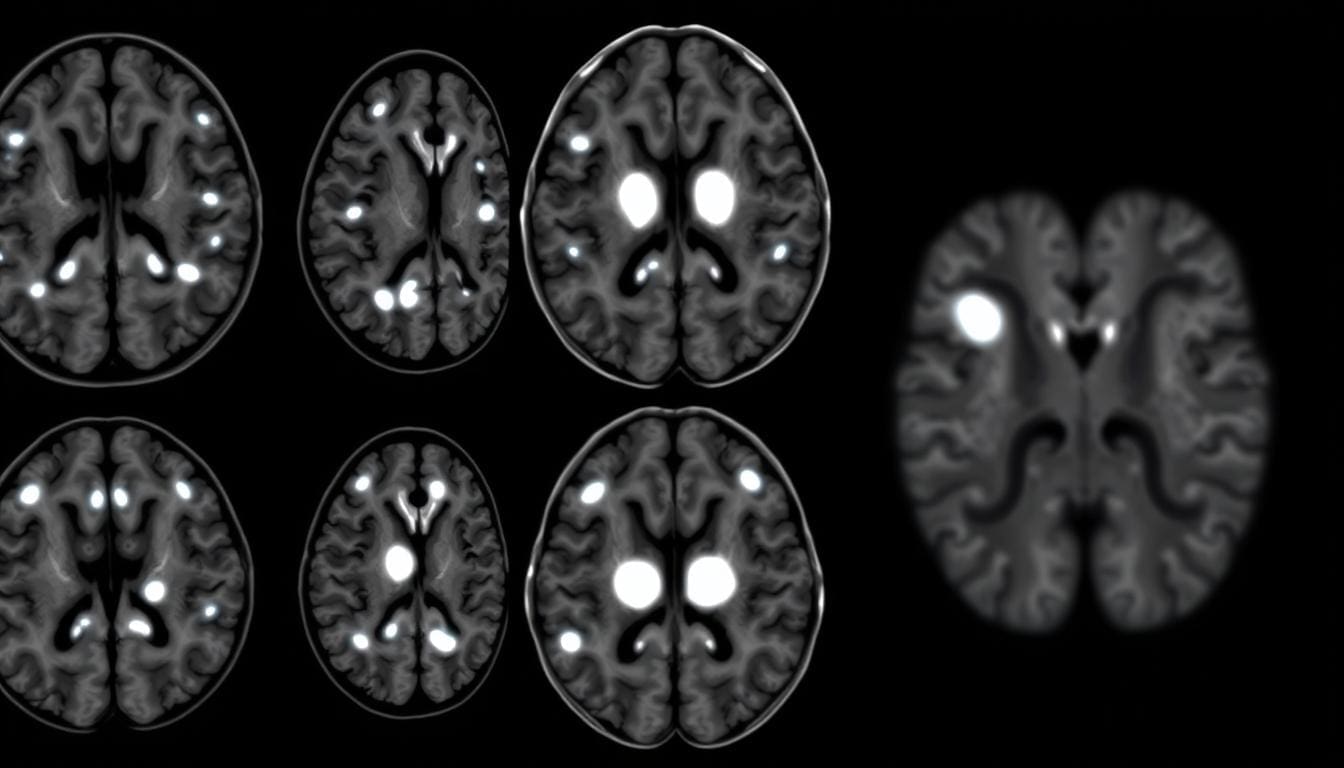

Brain MRI scans often show bright spots or white matter hyperintensities. These can worry both patients and doctors.

White matter hyperintensities are bright spots seen on MRI scans. They show up on T2-weighted and FLAIR images. These spots are in the brain’s white matter, which has myelinated nerve fibers.

How Normal Brain Tissue Appears Versus Abnormalities

Normal brain tissue looks different on MRI scans. It depends on the scan type. White matter hyperintensities, though, are very bright, mainly on T2-weighted images. Knowing the difference helps doctors make accurate diagnoses.

Some areas look brighter because of more water, inflammation, or lesions. The MRI sequence used can also change how bright they appear.

Each MRI sequence shows different things. For example, T2-weighted images are great for spotting water changes. This makes them good for finding edema or lesions.